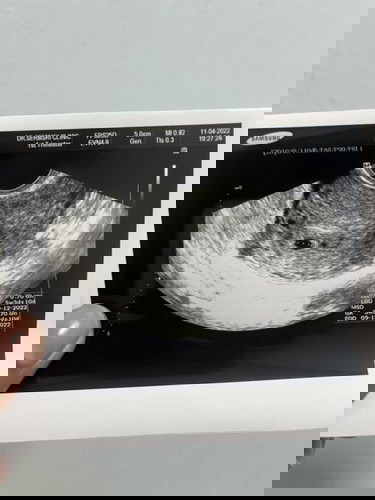

อายุครรภ์5สัปดาห์3วัน เห็นแค่ถุงตั้งครรภ์ปกติไหมค่ะ

แอบกังวลค่ะ คุณหมอบอกว่าเห็นแค่ถุงตั้งครรภ์ยังไม่เจอตัวค่ะ

ขอสอบถามเเม่ๆหน่อยค่ะ เราไปซาวเจอน้องครั้งเเรกตอน7 สัปดาห์ค่ะ เเต่อยากทราบว่ามีใครพอจะทราบมั้ยคะ ว่าตรงวงกลม ถุงๆ ข้างๆ ถุงน้องคืออะไรคะ เเล้วจะอันตรายมั้ยคะ

ปกติค่ะ เราก็เห็นแต่ถุง และถุงอยู่ในมดลูก อันไหนไม่แน่ใจ ตอนตรวจ ถามคุณหมอได้เลยนะคะ

ถุงตั้งครรภ์อยู่ในมดลูกปกติค่ะ ขอบนะคะ

ตรวจเจอแค่ถุง กังวลมากเลยค่ะว่าจะท้องลม🥺